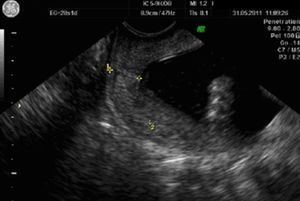

Se realizan controles ecográficos seriados semanales que resultan normales, en la semana 24 se observa una biometría acorde a las semanas de gestación con PFE de 617 gramos, ILA 11,5cm con laguna máxima de 3,4cm. En la ecografía transvaginal se aprecia longitud cervical de 28mm sin embudización en condiciones basales pero tras presión en fondo uterino se modifica a 23mm con embudización en «V», llamando la atención la existencia de imágenes hiperecogénicas sobre OCI compatibles con sedimento amniótico (fig. 1).

Durante su estancia hospitalaria cede la dinámica, no presenta nuevos episodios de metrorragia, los controles analíticos son normales (a destacar Hb de 11mg/dL y ausencia de leucocitosis), en los registros cardiotocográficos no se evidencia dinámica uterina y en la ecografía practicada se informa de feto en podálica con PFE de 1.200 gramos con LA normal (ILA de 16cm con laguna máxima de 6,8cm) longitud cervical de 11mm sin embudización (fig. 2) y sin apreciarse imágenes compatibles con barro amniótico.